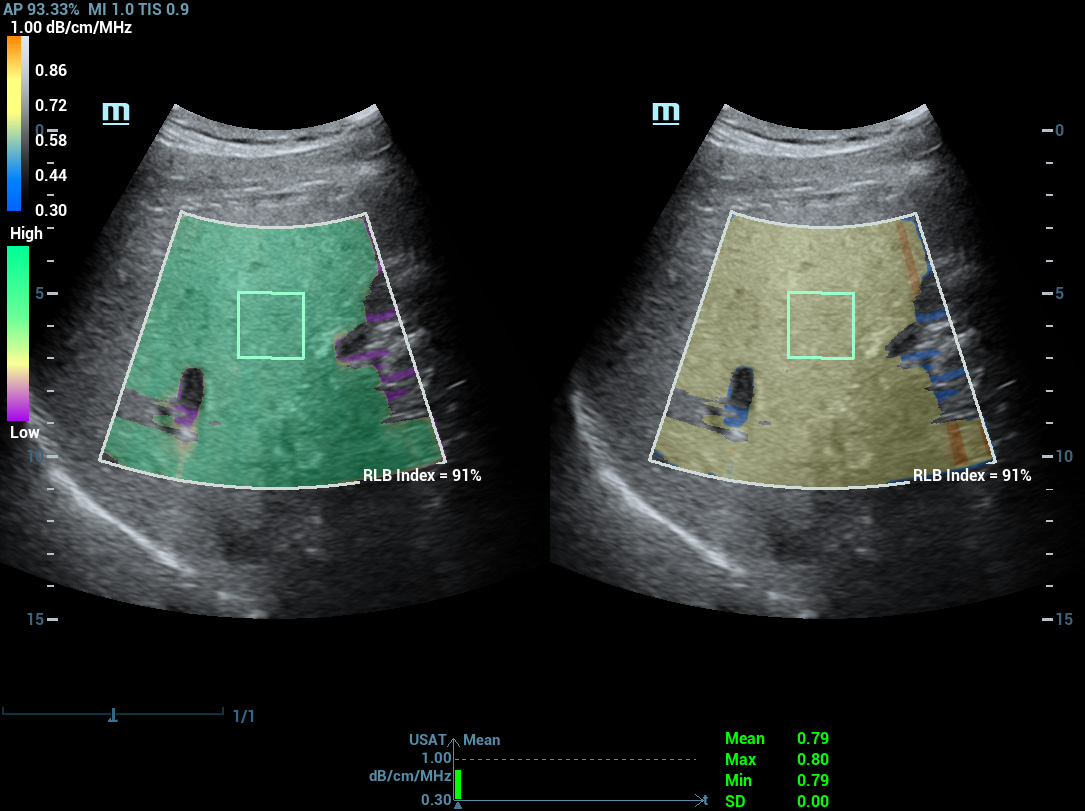

Laboratû°rio multiparamûˋtrico de fûÙgado gorduroso

Um novo salto para a pesquisa sobre esteatose

Laboratû°rio multiparamûˋtrico de fûÙgado gorduroso

O laboratû°rio multiparamûˋtrico de fûÙgado gorduroso oferece vûÀrias ferramentas de anûÀlise quantitativa baseadas em diferentes tecnologias. Permite a anûÀlise quantitativa da esteatose e melhora a sensibilidade na detec??o de fûÙgado gorduroso em estûÀgio inicial.